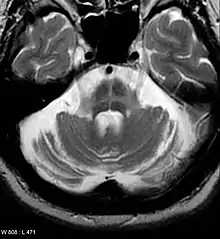

Imaging

Computed tomography (CT) scans of people with PD usually appear normal.[86] Magnetic resonance imaging has become more accurate in diagnosis of the disease over time, specifically through iron-sensitive T2* and susceptibility weighted imaging sequences at a magnetic field strength of at least 3T, both of which can demonstrate absence of the characteristic 'swallow tail' imaging pattern in the dorsolateral substantia nigra.[87] In a meta-analysis, absence of this pattern was highly sensitive and specific for the disease.[88] A meta-analysis found that neuromelanin-MRI can discriminate individuals with Parkinson's from healthy subjects.[89] Diffusion MRI has shown potential in distinguishing between PD and Parkinson-plus syndromes, as well as between PD motor subtypes,[90] though its diagnostic value is still under investigation.[86] CT and MRI are used to rule out other diseases that can be secondary causes of parkinsonism, most commonly encephalitis and chronic ischemic insults, as well as less-frequent entities such as basal ganglia tumors and hydrocephalus.[86]